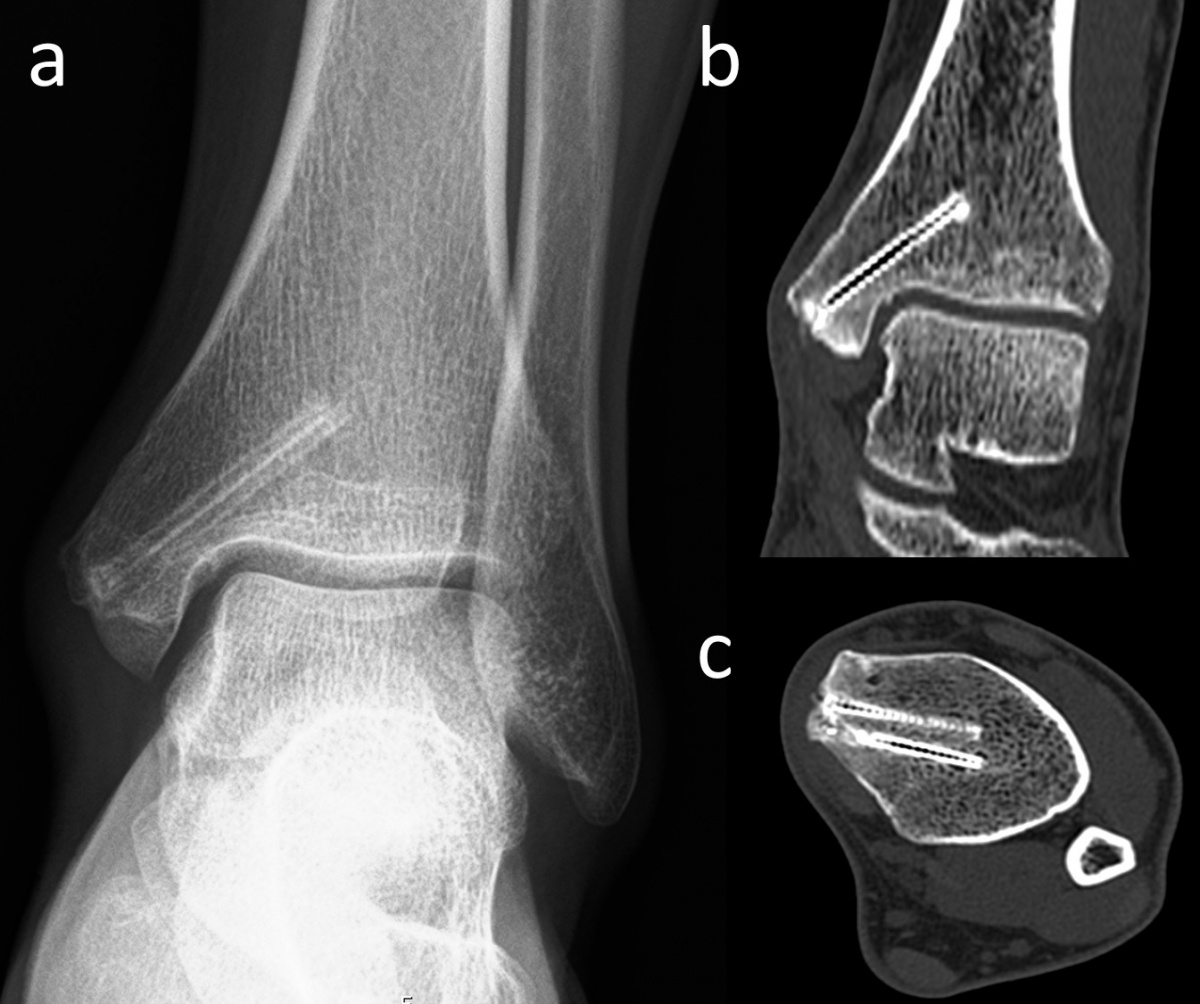

die mit zwei Magnesiumschrauben

fixiert wurde. (a) In der anterior-posterioren

Röntgenaufnahme des Knöchels in Monat 30

nach der Operation sind die Heilung der Fraktur

und die Umrisse der Schrauben sichtbar. (b)

Koronare und (c) axiale CT-Aufnahmen weisen

keine Gasansammlung im Knochen auf und die

Schrauben zeigen eine ähnliche Dichte wie die

umgebende Kortikalis.

In Bezug auf die Gasbildung und Resorption zeigt die Computertomographie ähnliche Ergebnisse wie die konventionellen Röntgenaufnahmen. In der Frühphase sind sowohl die Schrauben als auch die umgebenden Gasansammlungen deutlich sichtbar (Abbildung 5). Langfristige CT-Untersuchungen zeigen, dass das Gas vollständig resorbiert wird und damit vollständig verschwindet. Die Schrauben sind bis zu ihrer Umwandlung in kortikales Knochengewebe deutlich erkennbar (Abbildung 6). Adil et al. haben nachgewiesen, dass diese Konturen vier Jahre nach der Implantation in der tomographischen Dichtemessung ähnliche Hounsfield-Einheiten aufweisen wie die umgebende Kortikalis (17). Darüber hinaus erzeugen Implantate auf Magnesiumbasis – im Gegensatz zu konventionellen Metallimplantaten wie Titanschrauben – nur minimale Metallartefakte (18-20). Für die Nachbeobachtung der Patienten stellt dies einen signifikanten Vorteil dar.